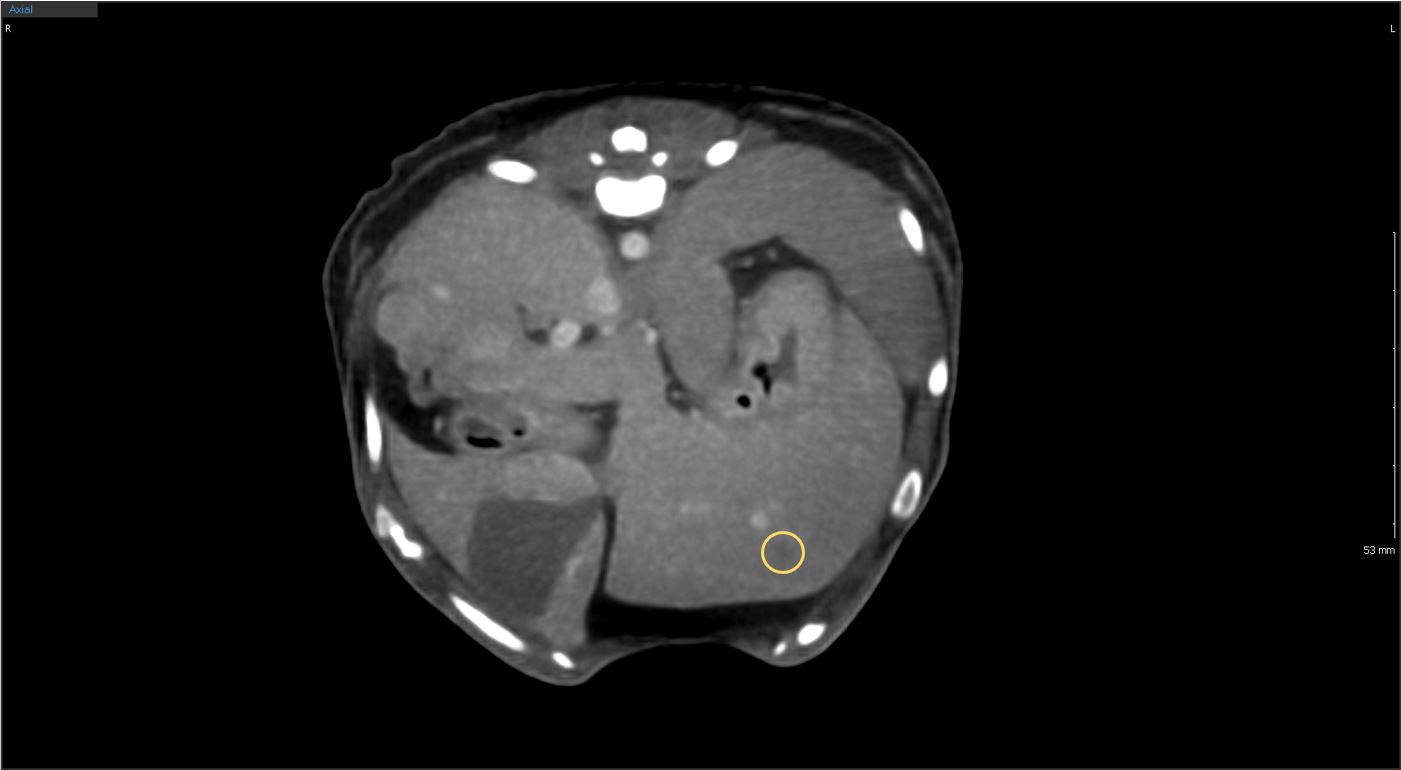

간결절 CT

간결절

복부 CT

복부

복부간, 비장, 소화기계, 비뇨기계 등의 복강의 장기